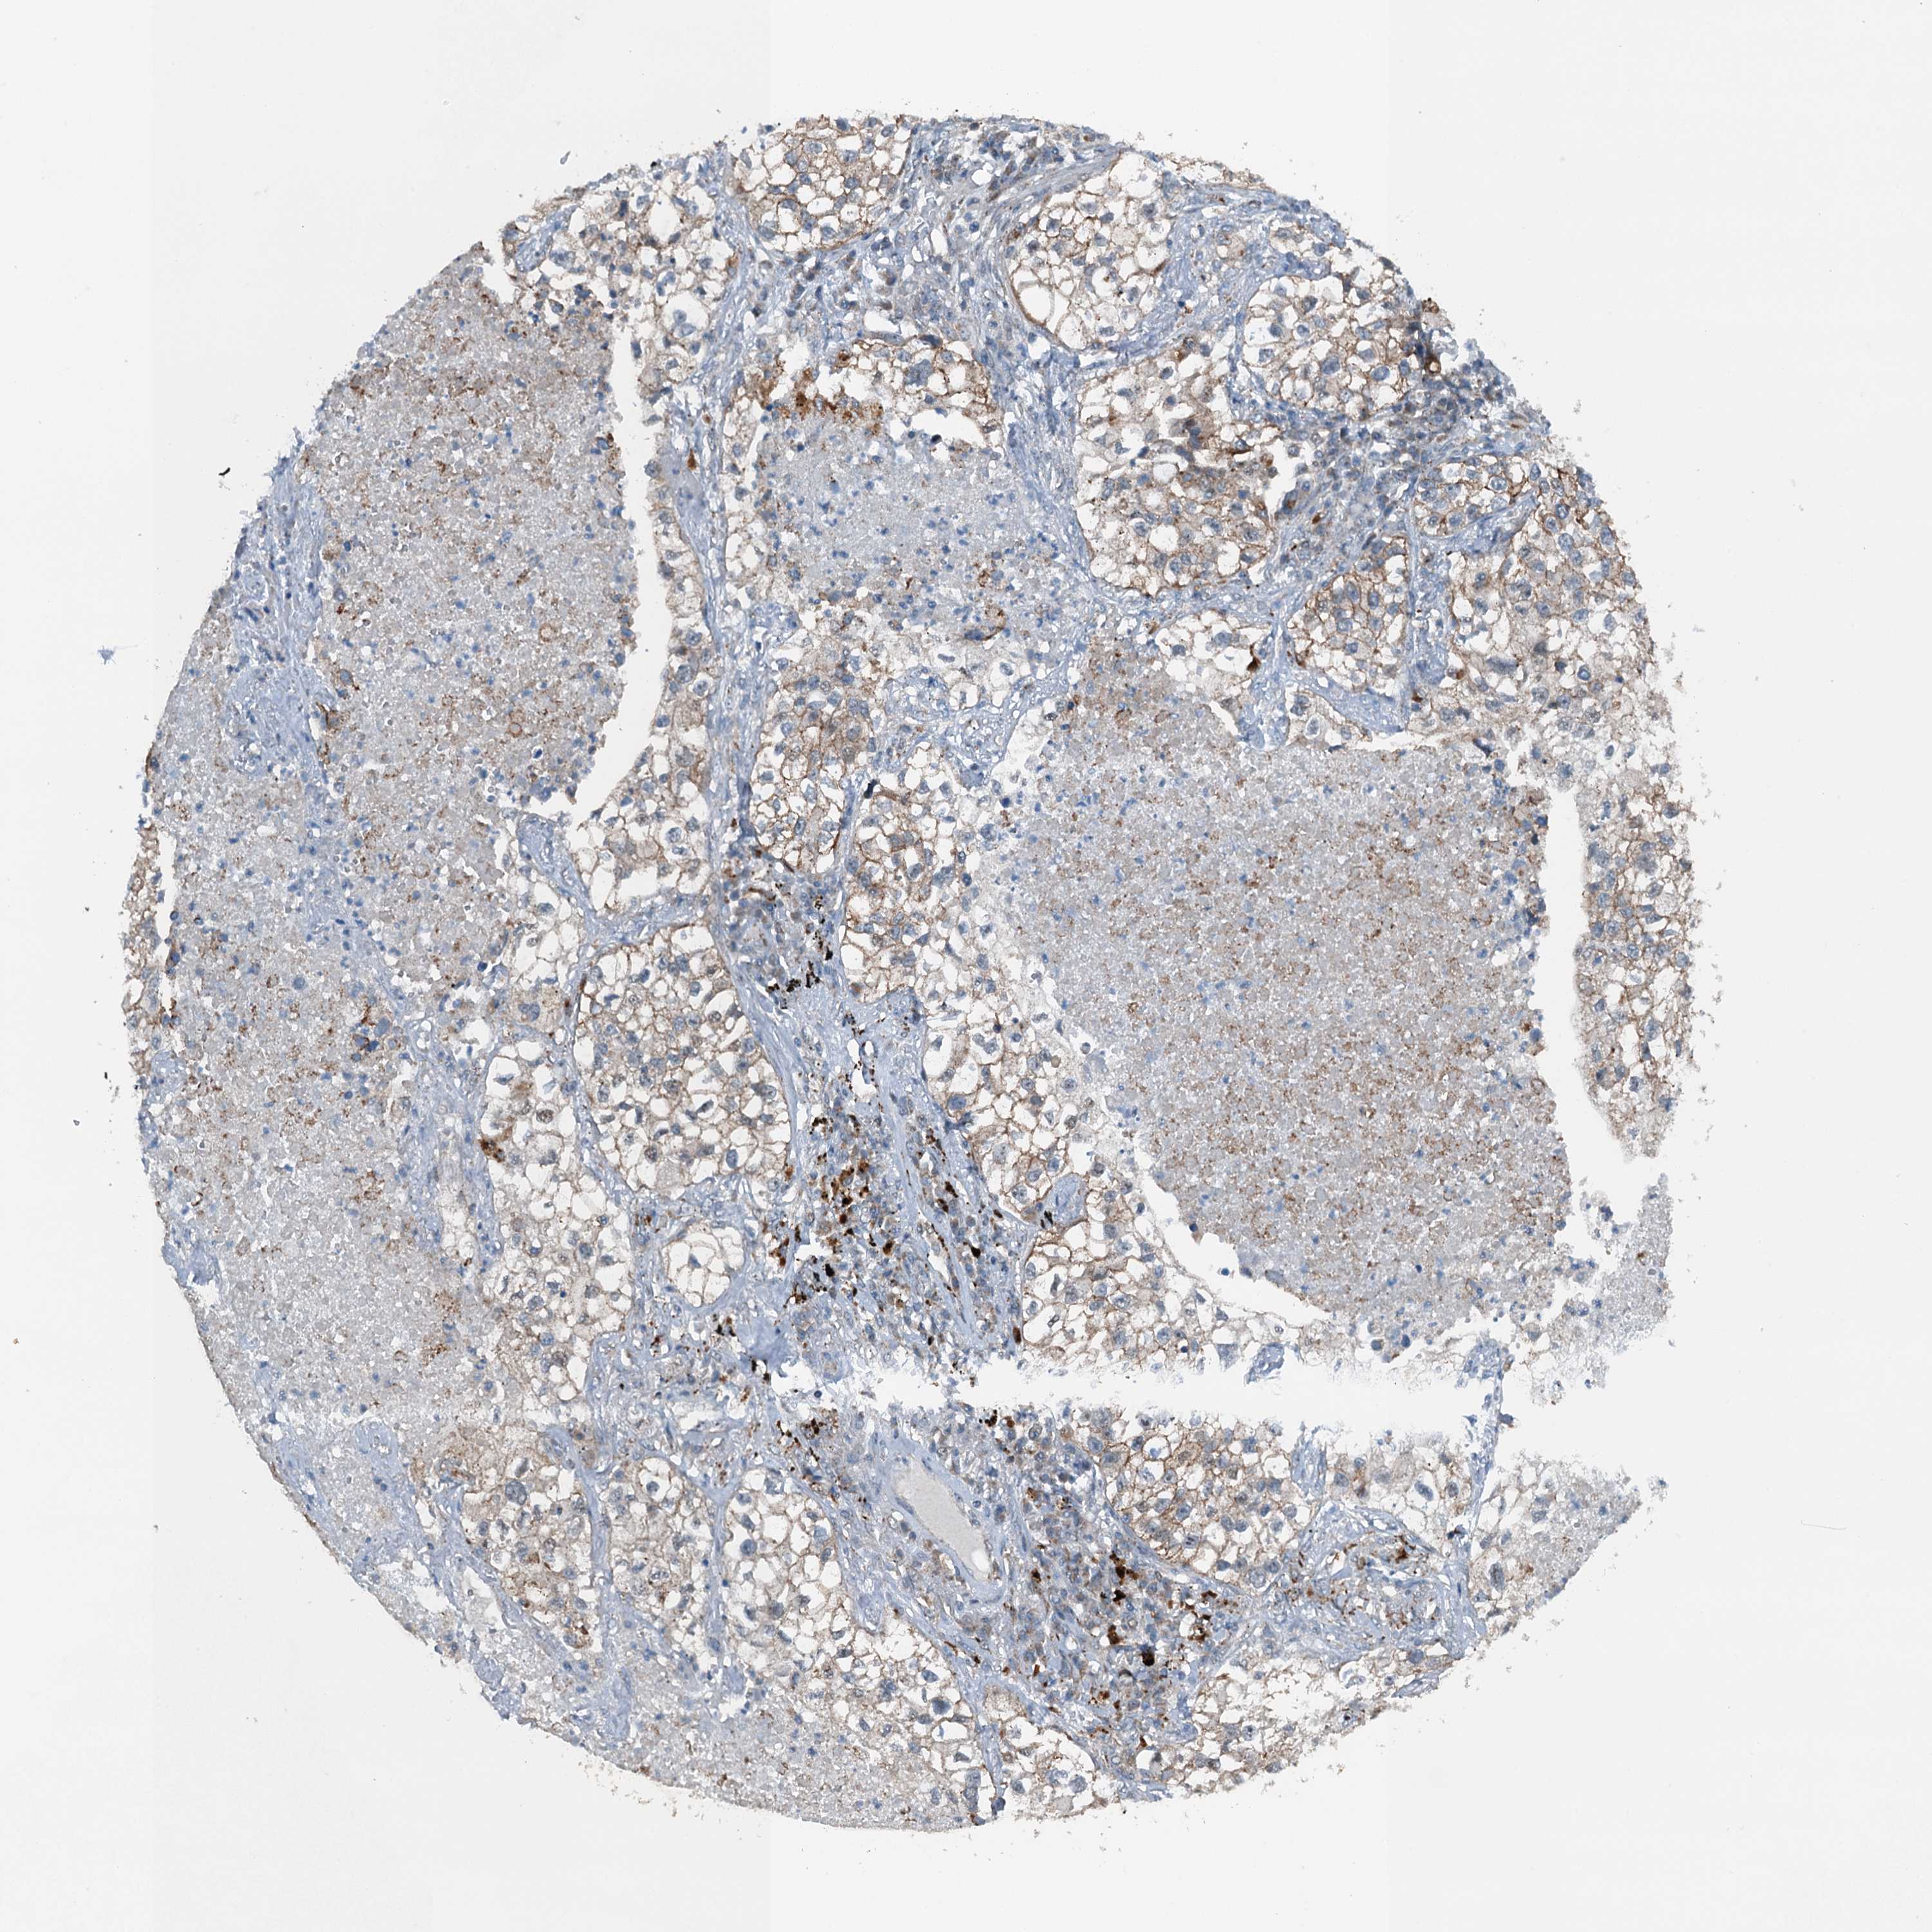

CANCER LUNG CANCER Show tissue menu

Lung cancer

Human cancer

Lung adenocarcinoma

Lung squamous cell carcinoma